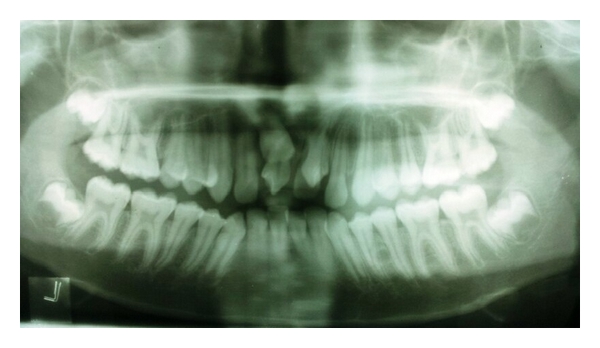

Radiographically examination revealed unerupted left central incisor. Two supernumerary teeth were found in maxillary central incisor region. One of the supernumerary teeth was partially erupted in left central incisor region in horizontal manner and the other was impacted. Root appeared to be incomplete (Figure 3). Partial erupted mesiodens showed invagination of radioopaque line towards the pulp suggesting dens invaginatus. As these mesiodens caused eruption failure of left central incisor and was esthetically unpleasant, extraction of both mesiodens was done. After extraction, patient was advised on wait and watch policy for eruption of the left central incisor.